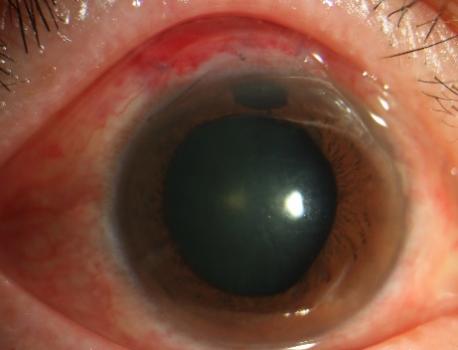

针对这一治疗困境,青光眼团队王建明主任、范雅稚副主任及王艳芬博士的深入讨论和分析,结合张阿姨的具体病情,最终决定为她实施单步隧道法---新型微创小梁切除术(SIGS)。这种术式以最小创伤实现高效降眼压,切口小、创伤小,能最大程度减少对眼部组织的损伤,降低并发症发生的风险,且该手术没有额外的一次性耗材,减轻了患者的经济负担,是当下挽救张阿姨视功能的理想选择。实施SIGS手术后第一天,张阿姨右眼眼压12mmHg,角膜基本透明,内皮皱褶明显减少,视力显著提升。术后张阿姨表示没有任何不适感,对治疗效果赞不绝口,并表示等角膜恢复后,一定还要请范雅稚医生亲自为她做后续的手术。由于手术非常微创、安全,张阿姨当天下午就踏上了回安徽的火车。范雅稚副主任介绍:“对于像张阿姨这样角膜条件差、病情复杂、又担心传统小梁切除术并发症的患者,切口小、创伤小、安全性高的SIGS无疑是一个理想的选择,同时也为后续微创手术提供了时间窗。”

术后第一天,未使用缩瞳药物及任何降眼压药物